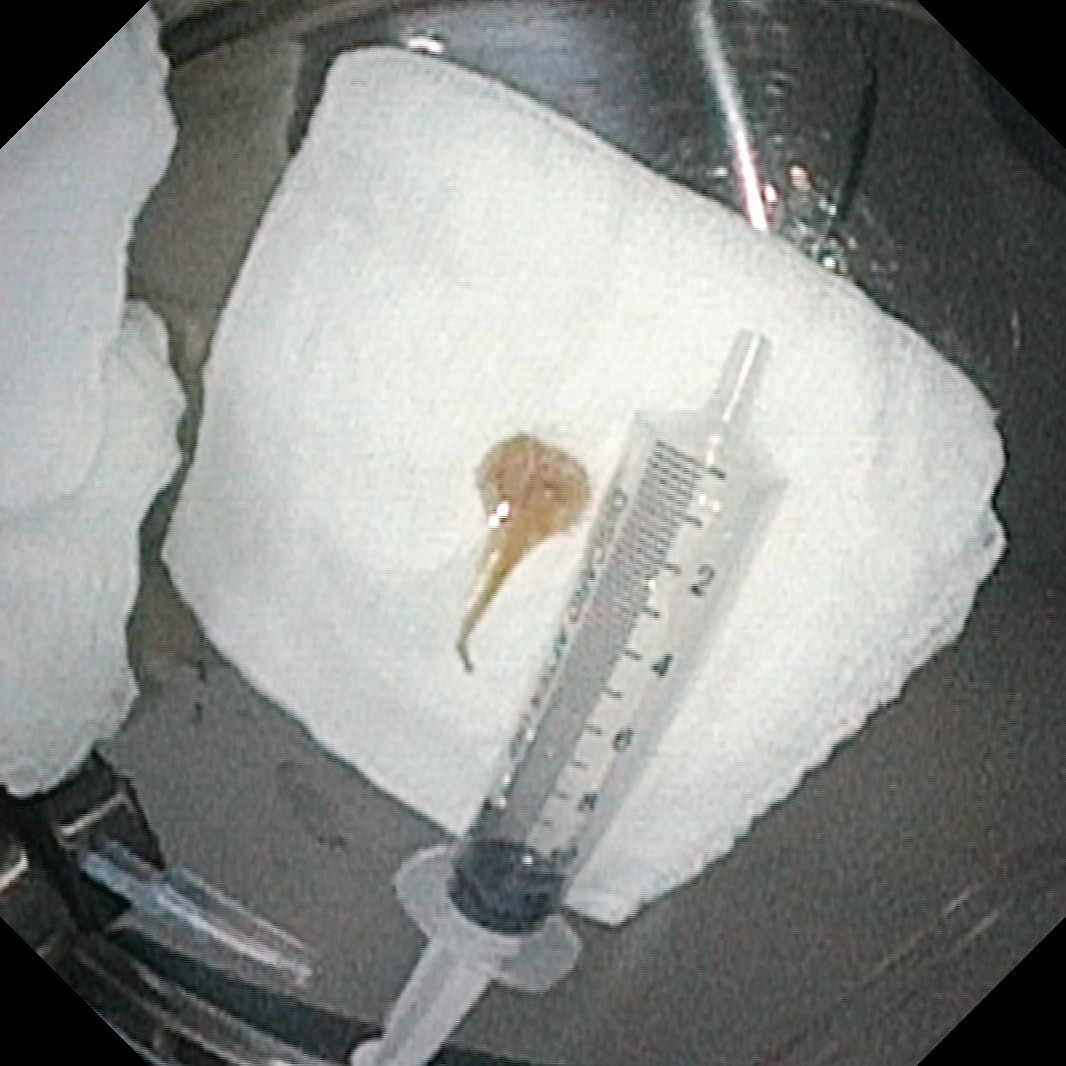

Xương cá được lấy ra - Ảnh BVCC

Ca nội soi diễn ra an toàn, thuận lợi, gắp thành công dị vật là xương cá nằm sâu trong phế quản, giúp khai thông đường thở, cải thiện rõ rệt tình trạng hô hấp cho người bệnh.